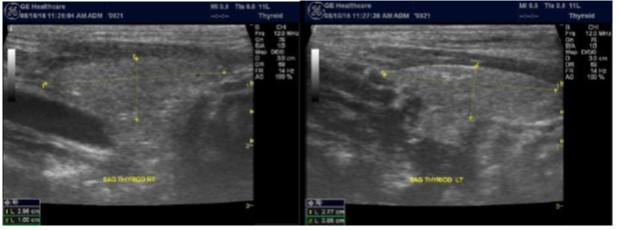

The superficial location of the thyroid gland renders it ideal for ultrasound examination 8. High resolution grey scale images can easily be obtained using high frequency transducer. In the transverse view, normal thyroid gland has the butter fly appearance, with left and right lobes connected with a narrow isthmus, Figure 1A. Both lobes can be imaged separately in the longitudinal plan, Figure 1B

Figure 1A.Normal thyroid gland transverse view